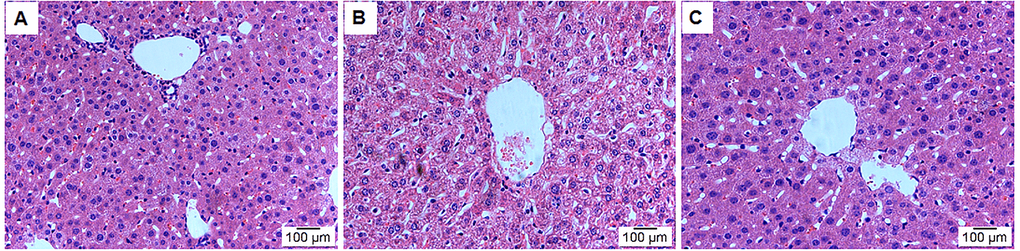

HE staining was used to analyse the effects of leonurine on the liver tissue histopathological features from aging mice. As shown in Fig. 5, the model group showed significant liver damage, including hepatocellular hydropic degeneration, necrosis, and inflammatory cell infiltration. However, there was an obvious increase in hepatocellular hydropic degeneration and necrosis upon treatment with leonurine compared to the mice in the model group. These findings suggested that hepatic pathological changes could be ameliorated by leonurine intervention.

Figure 5. Effect of leonurine treatment on liver histopathological alterations. (A) Control group; (B) Model group; (C) Leonurine group. H&E staining, magnification 200×.